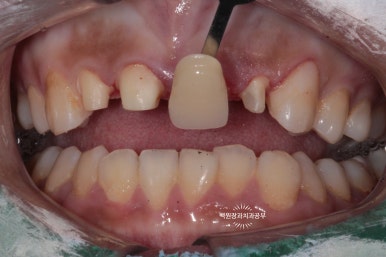

현재 치아의 색상을 여러개의 shade guide 를 사용하여 기록해둡니다.

이렇게 색상 가이드가 있어야만 작업하는 기공소에서 정확한 색상으로 제작이 가능합니다.

약 1주일간의 제작기간을 거친 후 최종 지르코니아 크라운 접착!!

완성된 지르코니아 크라운을 삭제된 치아에 부착해줍니다.

저희 금호동 치과.. 진짜 실력있는 치과 맞는 것 같습니다!! 앞니 지르코니아 크라운 치과로 추천해주세욤..ㅎㅎ

상당히 자연스러운 모습으로 제작이 잘 되었는데요, 무조건 밝은 색을 선택하기 보다는 인접한 치아들과 자연스럽게 조화를 이룰 수 있는 색을 택하였습니다.